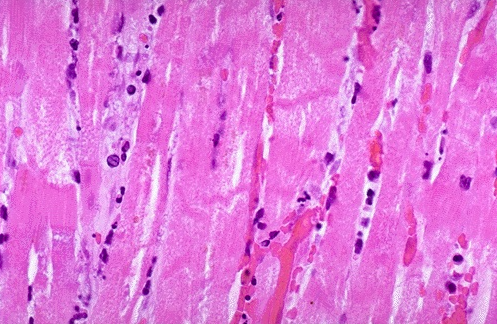

- High power microscopic view of the myocardium demonstrates an infarction of about 1 to 2 days in duration

- Myocardial fibers have dark red contraction bands extending across them. The myocardial cell nuclei have almost all disappeared

- Beginning acute inflammation

- Clinically, such an acute myocardial infarction is marked by changes in the electrocardiogram and by a rise in the MB fraction of creatine kinase